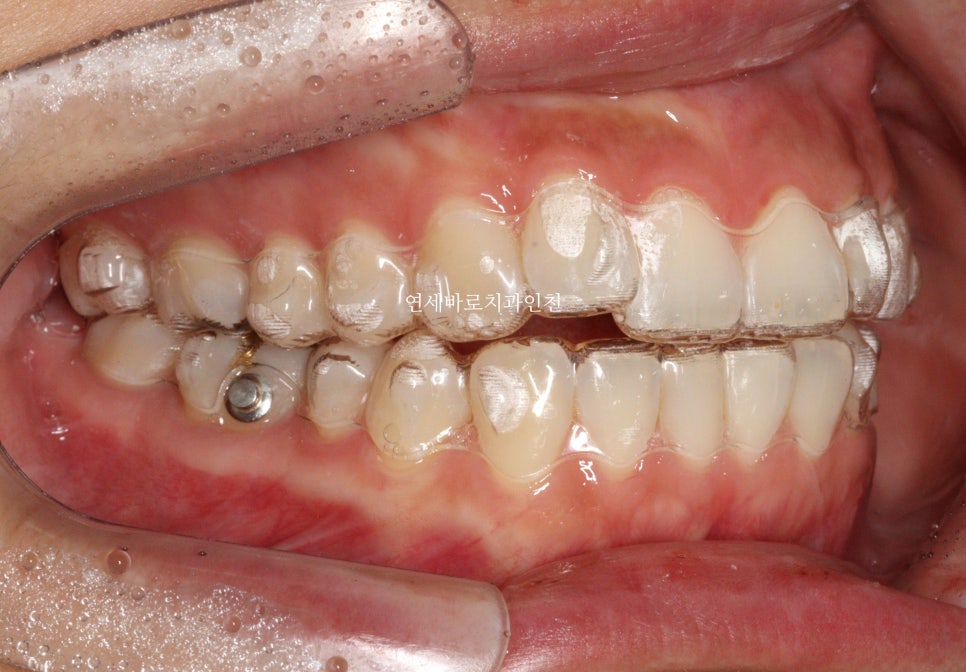

치료 초반의 모습입니다.

화살표 부분만 닿고 나머지는 다 닿지 않네요.

계획 그대로 진행되고 있는 겁니다.

무턱교정을 위해서는 위쪽 치아가 전체적으로 위쪽으로 올라가야합니다.

철사교정에서는 한덩어리로 잡고 한번에 올리지만

인비절라인에서는 다양한 옵션이 있는데, 이 환자분은 앞니, 그리고 어금니, 작은어금니를 나눠서 진행했습니다.

사진상 보이는 #미니스크류 도 사용하였습니다.

인비절라인 단독으로는 치료의 범위가 좁을 수 있지만, 미니스크류와 함께라면 조금 더 넓은 범위의 치료를 할 수 있습니다.